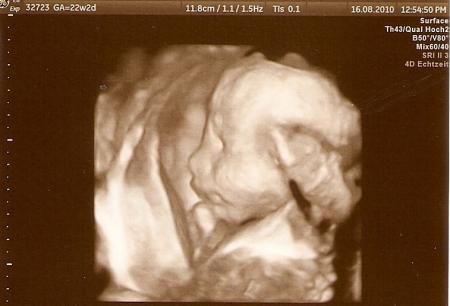

die Beine und Füße, liegt Bel, darum verkehrt herum.

Bild zu